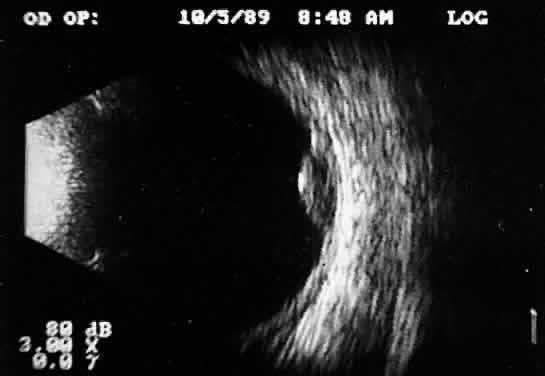

Choroidal malignant melanoma, perhaps the most widely studied intraocular mass lesion, has the most reproducible and reliable A-scan pattern. Usually, the initial echo seen in A-scan is a high-amplitude spike secondary to the strong vitreoretinal surface echo overlying the tumor mass. Once the examining sonic beam has passed into the tumor tissue, a rapidly declining amplitude cadence is noted, a consequence of increasing ultrasonic tissue homogeneity. Clinical knowledge of the typical microscopic tumor pattern of tightly packed, homogeneous small cells makes anticipation of relatively low reflectivity possible (Fig. 10). This same low-amplitude reflectivity in B-scan imaging produces a picture that makes the melanoma mass appear hollow. Often, tumor-infiltrated choroid also appears dark (Fig. 11). This change in the normally highly reflective choroidal tissue is widely but inaccurately called choroidal excavation. The terms “hollowing” and “choroidal excavation” are misleading because these tumors are not hollow and the choroid is not excavated. Nevertheless, these terms have been used so frequently in past literature that any change in vocabulary is unlikely.

Fig. 10. Contact B-scan and simultaneous A-scan: choroidal malignant melanoma. Note the strong initial echo from the overlying retinal tissue, followed by a rapid decline in A-scan echo amplitude within the deeper tumor tissue, a consequence of increasingly homogeneous tissue. High reflectivity is again seen at the level of the sclera and orbit.

Fig. 11. Contact B-scan: malignant melanoma, demonstrating hollowing and choroidal excavation.